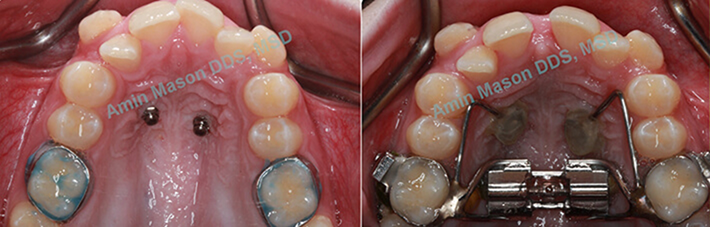

TADs Used to Open Maxillary Suture in Older Patients

Adults patients presented with narrow maxilla and crossbite. TAD-supported expanders were used to open the maxillary suture instead of surgical procedure.